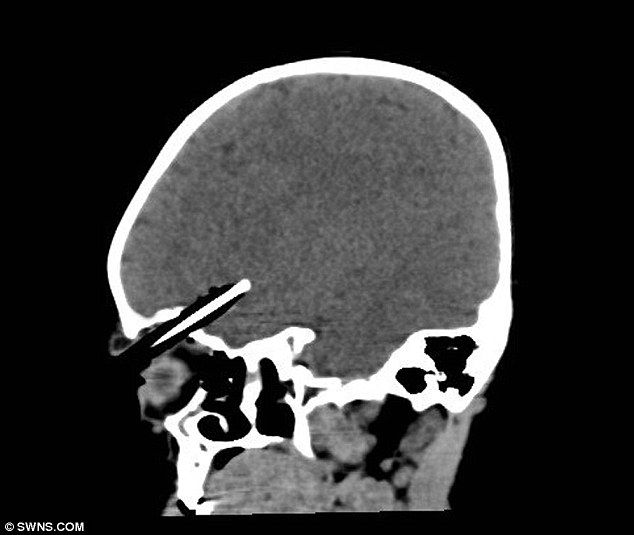

Двухлетняя девочка Рен Бовелл несла в руках карандаш и случайно упала с лестницы возле дома. Карандаш заострённой частью вонзился ей в глаз, девочку сразу доставили в больницу где четыре часа врачи боролись за её жизнь удаляя карандаш из черепа.

По словам врача девочке очень повезло,карандаш остановился в миллиметре от мозга и нечего не задел. Сейчас жизни девочке ничего не угрожает.